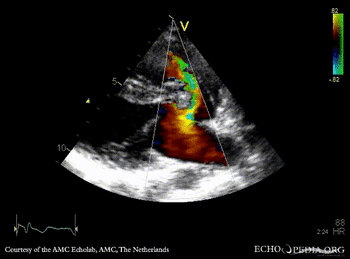

| Courtesy of: AMC Echolab, AMC, The Netherlands | |

| PLAX | PLAX: Color Doppler, ????? |